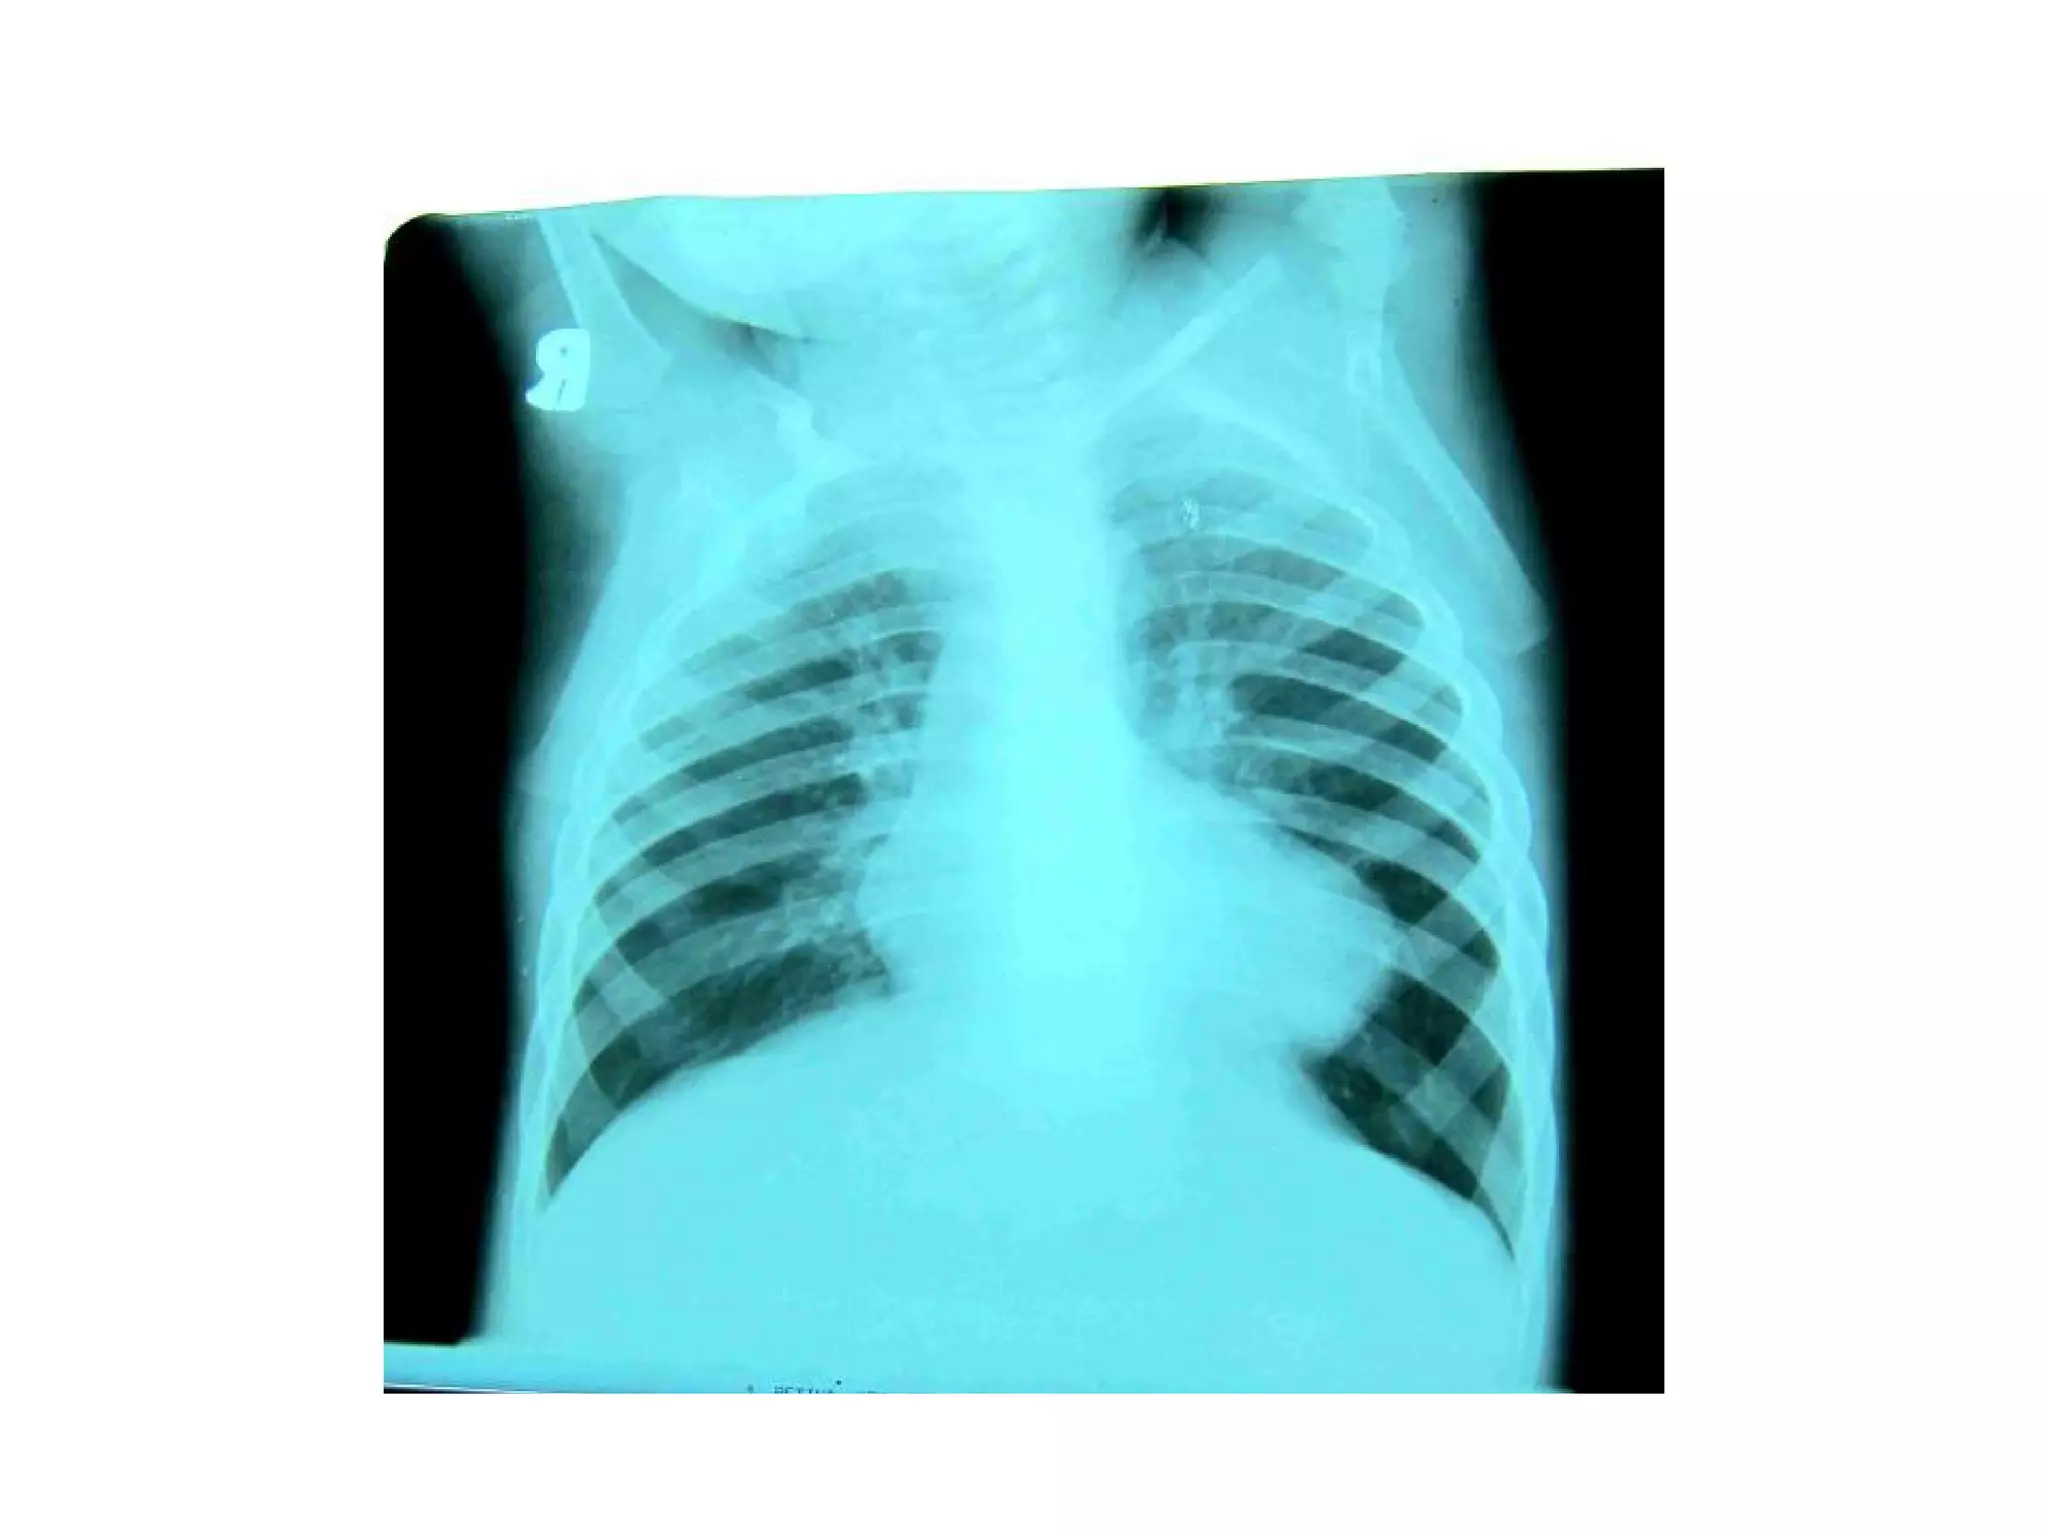

• Chest X-ray : The classical appearance in TOF is of a

‘boot shaped heart’ due to right ventricular hypertrophy

and reduced central pulmonary markings .The lung fields

may be oligaemic.